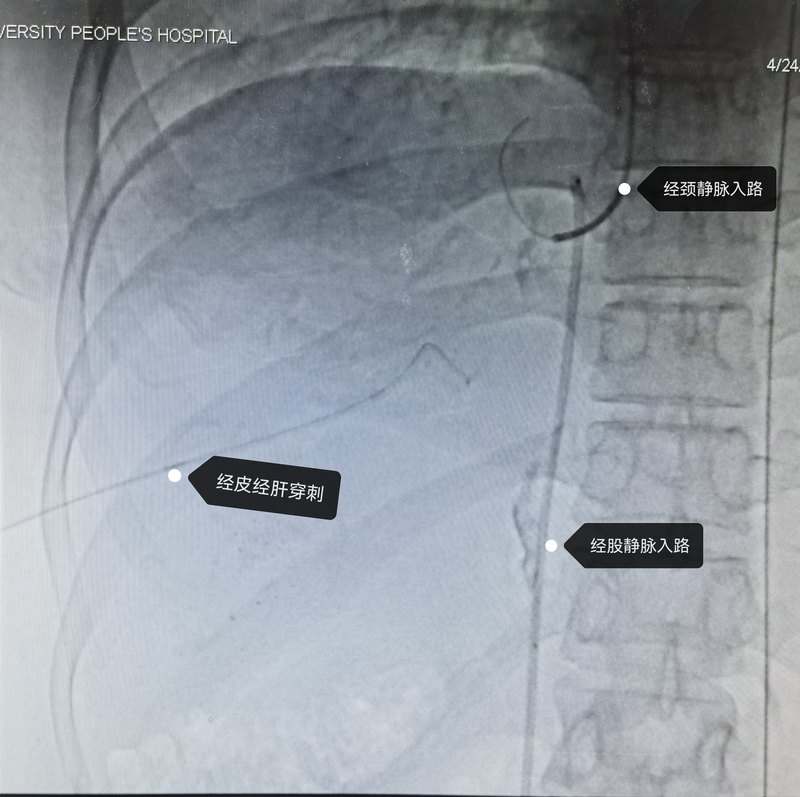

布加綜合癥是肝后型門脈高壓,伴或不伴下腔靜脈梗阻的一組疾病。經(jīng)常表現(xiàn)為肝大脾大,腹水,可以有上消化道出血,黃疸表現(xiàn)不重。一些病例可以繼發(fā)于肝小靜脈閉塞或肝靜脈血栓形成,另有一些病例可以由隔膜導(dǎo)致肝靜脈和下腔靜脈梗阻。許多病例可以通過微創(chuàng)介入的方法處理,微創(chuàng)介入主要是有三條通路:經(jīng)股靜脈通路,經(jīng)頸靜脈通路,和經(jīng)皮經(jīng)肝穿刺通路